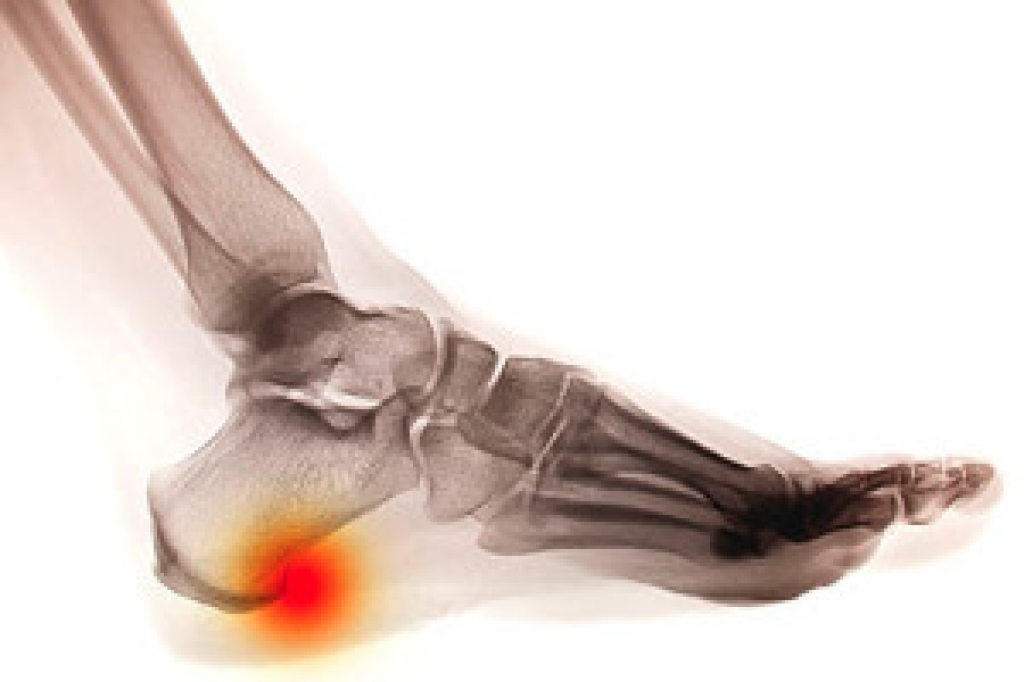

Many patients are aware of the benefits of foot massages. These are often performed as foot therapy, which can help the feet to feel better and ease any existing pain. An effective way to begin a foot massage is by gently placing the palms on both sides of the foot, while twisting back and forth. Additionally, having the arches massaged can benefit the bottom of the foot. Flexibility may be increased when the toes are stretched as well. If there is pain in the Achilles tendon region, it may help to focus on massaging that area of the foot. If you would like more information on how foot massages may support general well-being, it is suggested that you schedule a consultation with a podiatrist.